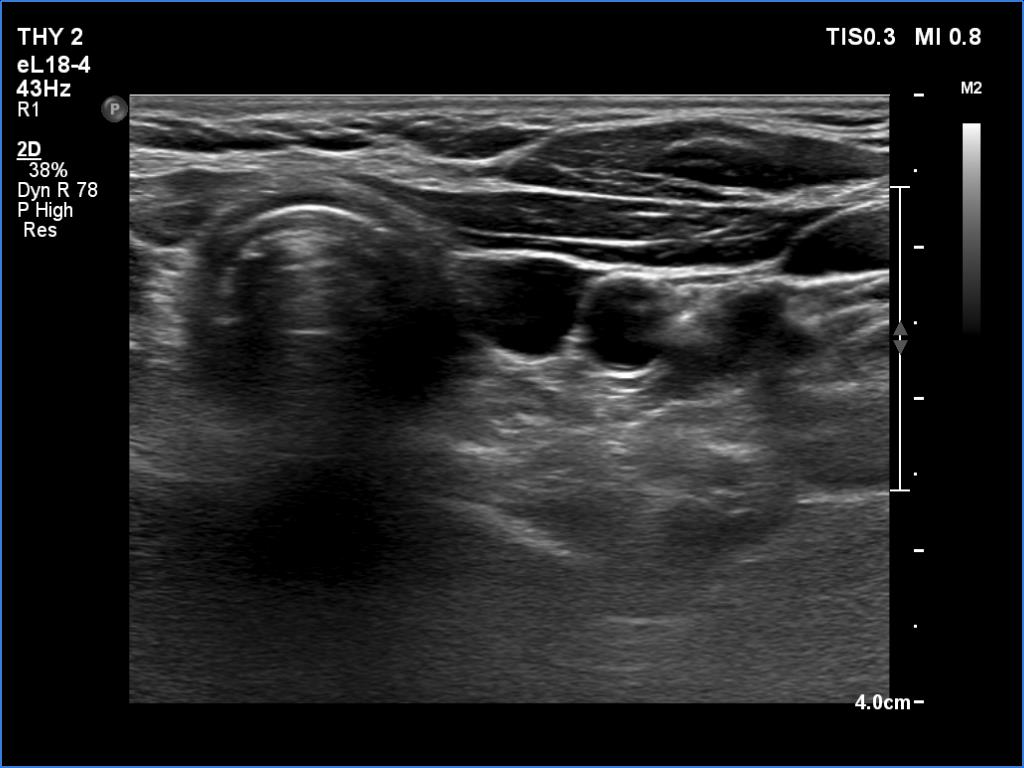

First examination (first two rows of images)

Clinical data: A 19-year-old woman came to a yearly follow-up examination. She has been operated on and has got radioiodine therapy for a T4 papillary cancer for six years. Two years after the surgery, a cystic lesion was found in the left thyroid bed with the diameters of 7x5x12 mm, width, depth and length, respectively. The largest diameter of the lesion ranged between 9 and 13 mm in the upcoming years, the thyroglobulin levels were always below 0.2 ng/mL.

Ultrasonography revealed a cystic lesion in the left thyroid bed. The dimensions of the cyst were 8x6x13 mm, width, depth and length, respectively.Suggestion: to continue with the daily 125 microgram levothyroxine. TSH in a year, in the event of pregnancy at once.